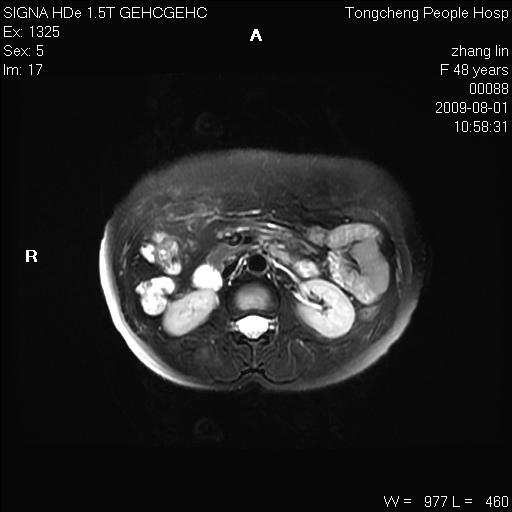

女,48岁。健康体检,彩超发现右肾占位性病变。平素健康。

临床诊断:右肾占位性病变,性质待定(囊肿?肿瘤?)。

上中腹部mr平扫+增强扫描,图像如下:

右肾上极见一类圆形病灶,t1wi呈等信号t2wi呈等高混杂信号,三期增强无强化,边界清---考虑囊肿出血。

同反相位均表现为等信号,病变无强化,考虑含蛋白的囊肿可能,弥散加权相或许有些帮助,